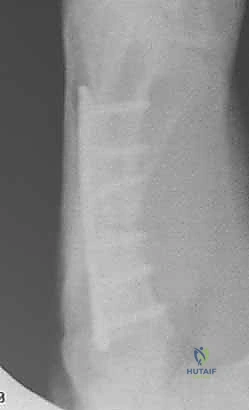

2. التثبيت الداخلي بالصفائح والبراغي المصغرة (Mini-Plates & Screws)

في حالات الكسور المتفتتة (Comminuted) أو الكسور الحلزونية الطويلة التي تميل للانزلاق، يلجأ الدكتور هطيف إلى التثبيت الداخلي المفتوح (ORIF). يتم استخدام صفائح معدنية دقيقة جداً (مصنوعة من التيتانيوم) تتناسب مع حجم عظام اليد.

* الميزة: تثبيت صلب وقوي جداً (Rigid Fixation)، مما يسمح للمريض ببدء العلاج الطبيعي وتحريك أصابعه في اليوم التالي للعملية، وهو أمر بالغ الأهمية لمنع تيبس الأوتار.

خطوات التثبيت الجراحي - توثيق بصري (Intraoperative Imaging)

يحرص الدكتور هطيف على توثيق خطوات العمل الجراحي لضمان أعلى مستويات الدقة. نستعرض هنا مجموعة من الصور من داخل غرفة العمليات توضح مدى تعقيد ودقة هذه الجراحات:

معرض الصور الشعاعية: تقييم النتائج الجراحية (Post-Op X-rays)

النجاح الحقيقي يُقاس بالاستعادة المثالية للشكل التشريحي للعظم. توضح هذه الصور الشعاعية بعد الجراحة الدقة المتناهية في إعادة محاذاة العظام وتثبيتها.

التثبيت المحكم يسمح بالشفاء العظمي الأولي (Primary Bone Healing) دون تكوين كتلة عظمية كبيرة (Callus) قد تعيق حركة الأوتار المنزلقة فوقها.